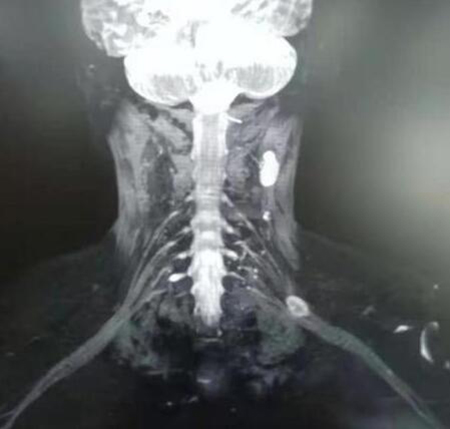

深受手臂发麻困扰鲁女士一直在积极治疗,但左臂发麻、无力的症状非但没有缓解,反而逐渐加重。1个月前,鲁女士到我院门诊就诊,此次就诊竟然揪出了手臂发麻无力的元凶是“臂丛神经鞘瘤”。

神经鞘瘤 ( neurilemoma/Schwannoma ) 源自神经髓鞘 Schwan 细胞的良性肿瘤,是周围神经性肿瘤中最常见的一种。可发生于任何有神经的部位,多见于四肢屈侧较大的神经干,上肢多于下肢;可见于任何年龄,以青壮年(20—50岁)居多;90% 为单发。肿瘤多沿神经干的一侧偏心生长,大小不一,直径多<5cm ,极少恶变。

为此,骨外三科进行了科室疑难病例讨论,为鲁女士量身定制了手术方案。手术看似很简单,只要将肿块从神经上完整剥离出来即可。但这恰恰也是这台手术难度最大、危险最高、挑战最高的地方,因为肿块被神经紧紧包围,在剥离过程中必须小心、谨慎,最大程度确保神经不受伤害,保证术后病人患侧肢体活动功能,这样手术才算成功。

最终,肿块被完整剥离;术后3天,鲁女士恢复良好并顺利出院,未出现上肢的感觉和运动障碍,上肢麻木及无力好转。